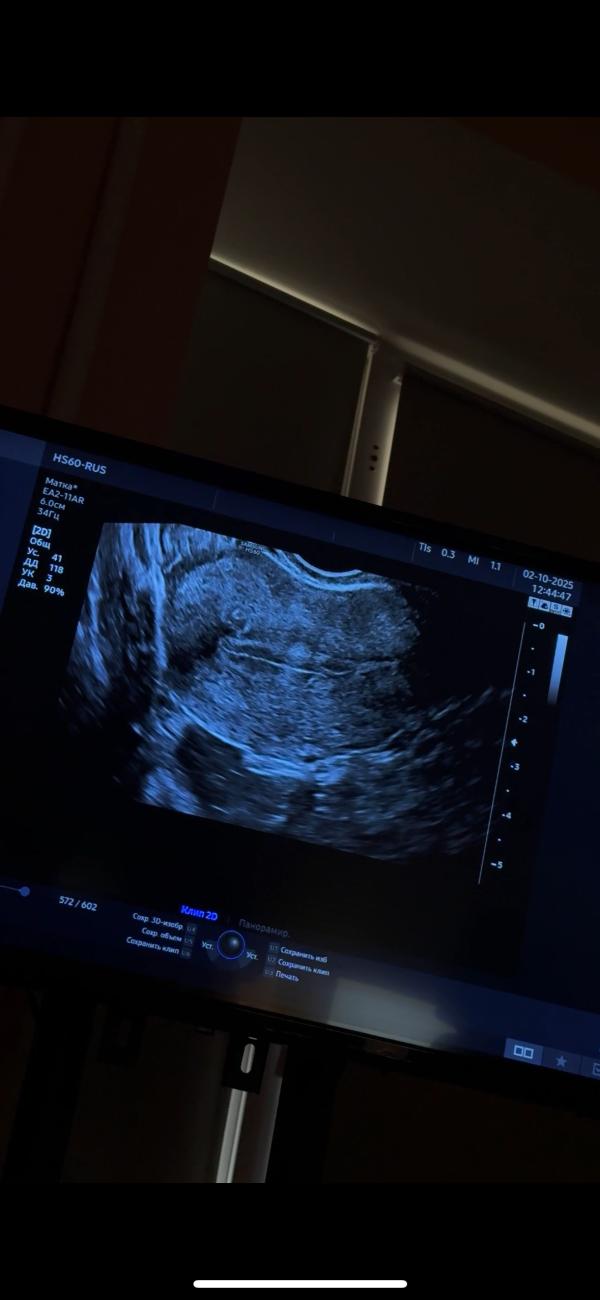

Что может быть на эндометрии после пункции фолликулов

Женсовет, что это может быть на эндометрии?

Кровотока нет, узист сомневается, что это полип

1 Цикл после пункции фолликулов